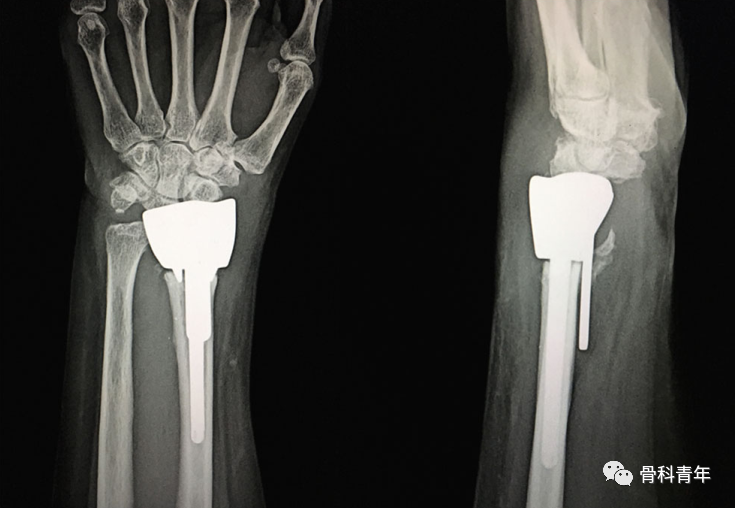

一、桡骨远端髓内钉

髓内钉技术广泛应用于长骨骨干骨折,闭合或有限切开复位有效降低医源性因素对血运的破坏,并具有良好的轴心固定生物学优势。桡骨远端髓内钉出现较晚,该技术适用于完全关节外骨折及简单的关节内骨折,对关节内粉碎骨折并不适用

桡骨远端骨折髓内钉固定的前提是闭合复位效果满意,克氏针临时固定后,通过桡骨茎突开口,自腕背侧第1/2间室间隙进入。该技术存在潜在的损伤包括桡神经分支损伤,螺钉穿入下尺桡关节或桡腕关节等。